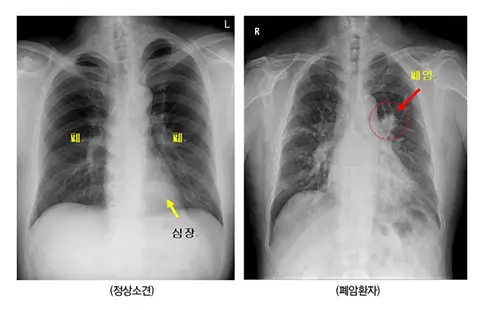

폐암 진단 방법

폐암을 진단하기 위해서는 여러 가지 검사를 통해 암의 존재 여부를 확인하고, 병기를 결정하게 됩니다. 여기에는 영상 검사, 조직 검사, 그리고 유전자 검사 등이 포함됩니다.

저선량 흉부 CT

- 저선량 흉부 CT는 폐암의 조기 진단에 가장 효과적인 검사 방법입니다. 이 검사는 X선 검사보다 더 민감하게 작은 결절을 발견할 수 있으며, 특히 고위험군(흡연자, 가족력이 있는 경우)에게 권장됩니다.